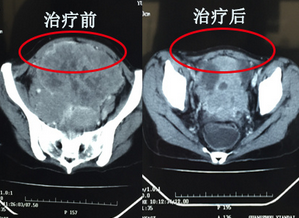

目前,玉丽雅已经接受了5次介入治疗,2次冷冻治疗,在这过程中,肿瘤从原来的14cm已经缩小到8cm。玉丽雅的主治医院庞医生告诉我们,她的治疗效果很明显,继续接受治疗,肿瘤能进一步缩小,让我们来期待又一个抗癌奇迹吧。